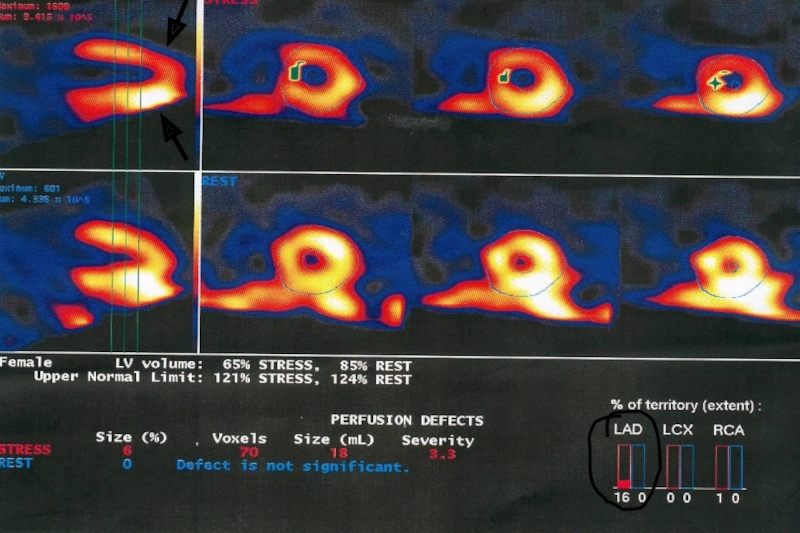

Слайд 21Чувствительность и специфичность SPECT (однофотонная эмиссионная компьютерная томография миокарда)

Чувствительность

и специфичность ЭКГ-синхронизированной SPECT миокарда для диагностики коронарной болезни сердца

превышают 90%

Слайд 23SPECT миокарда в стратификации риска

Нормальные результаты SPECT (в частности SSS)

означают очень доброкачественный прогноз, несмотря на данные ЭКГ и

ангиографические находки.